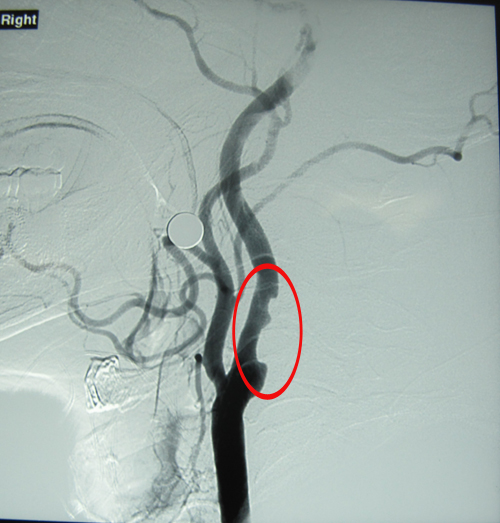

DSA:双侧颈内动脉起始部、左颈总动脉膨大处、左侧颈内动脉虹吸段及左侧大脑中动脉多发动脉粥样硬化斑块;左侧颈内动脉起始段管腔重度狭窄。

右侧颈内动脉局限性溃疡斑块